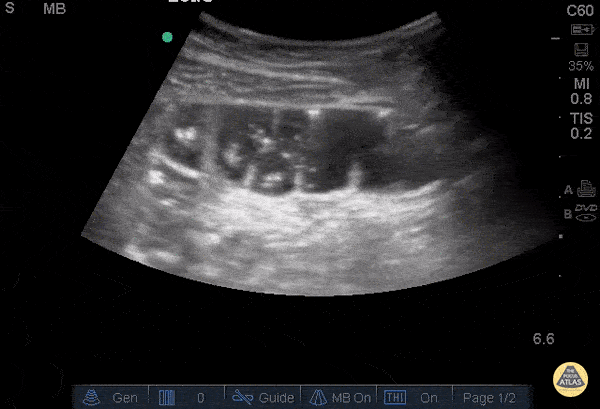

Bowel-GI - Incarcerated Hernia with SBO

29 yo F with known hernia p/w sudden onset abdominal pain 2hrs ago. Given a concern for an incarcerated hernia, POCUS was done showing the incarcerated loop of bowel (hypoechoic structure on the left), as well as evidence of an SBO. In addition to a dilated loop (+LR of 15 for 3 loops >2.5cm), the hyperechoic lines along the bowel represent valvulae conniventes which are suggestive of an obstructed loop of jejunum. Patient happened to be pregnant (17wks, FHR and motion also confirmed by POCUS), but was taken emergently to the OR for open repair with mesh and was discharged the next day. Bryan Jarrett, MD - SUNY Downstate/Kings County